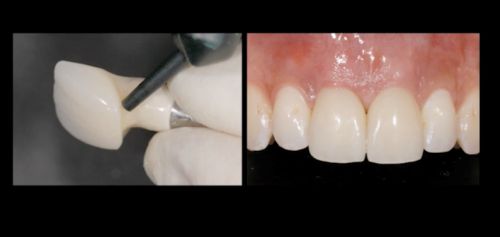

Фото. Фиксированы временные реставрации для формирования мягких тканей.

Фото. Сформированные мягкие ткани готовы для фиксации постоянных коронок.

Фото. Фиксированы постоянны цельно-керамические рестарвации (коронки).

Так выглядит современный протокол по замещению имплантатом одного зуба